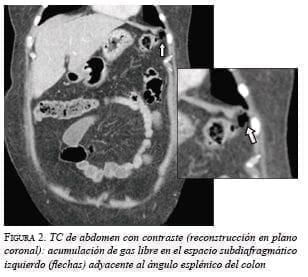

En las tres pacientes, la TC abdominal con contraste mostró el neumoperitoneo pericólico o localizado a menos de 5 cm del asa inflamada sin aire distante (figuras 2 y 3); dos presentaron divertículos en el ángulo esplénico, colon descendente y sigmoide, y una en el colon sigmoide únicamente.

La diverticulitis en las tres pacientes fue de grado Ia por la presencia de inflamación pericólica y la clasificación de Hinchey modificada por Wasvary, y grave por la presencia de aire externo a la luz intestinal en la TC y la clasificación de Ambrosetti (tabla 1) 5.